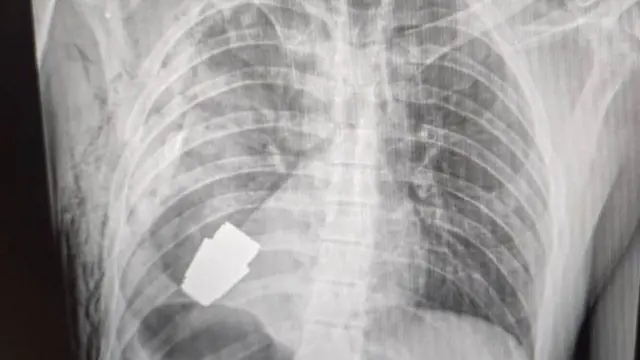

युक्रेनमधील एका सैनिकाच्या छातीमधून न फुटलेलं ग्रेनेड काढण्यात आलं आहे.

युक्रेनच्या सैनिकी वैद्यकसेवेने फेसबूकवर त्याचा एक्सरे फोटो प्रसिद्ध केला आहे. या सैनिकाच्या हृदयाच्या अगदी जवळ हे ग्रेनेड असल्याचं दिसतं.

हे ग्रेनेड त्या सैनिकाच्या छातीत कसं गेलं हे अद्याप समजलेलं नाही. पण ते VOG ग्रेनेड असल्याचं समजतंय. ते 4 सेंमी. आकाराचे असून त्याचा 400 मीटर अंतरापर्यंत मारा करता येतो.